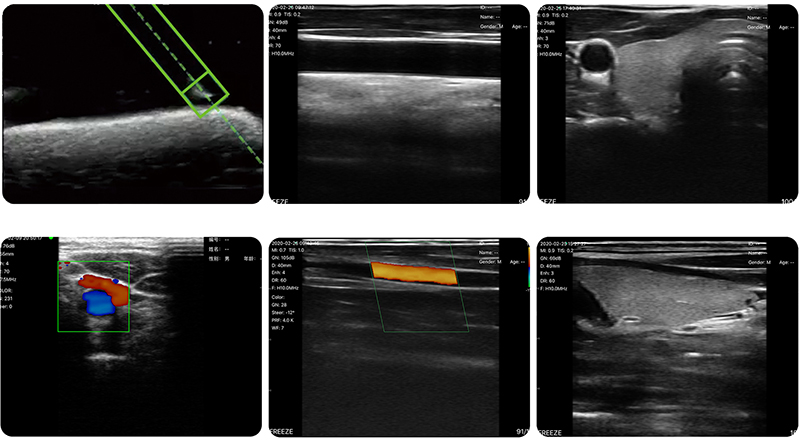

超声成像显示穿刺针叠加磁场位移、角度定位显示穿刺针,实现多方位且交叉验证的更有保障的穿刺针可视化,让穿刺更加精准,提高穿刺介入的成功率,降低穿刺介入的难度,且不用依赖穿刺架而操作更加简易。

内置于掌超里面的磁传感器获取环境磁场矢量和磁化后带磁性的穿刺针产生的磁场矢量,发送至运算单元中,计算穿刺针的位移、角度,并生成位移、角度信息的图案,叠加到超声图像上一起显示。

• 穿刺辅助功能:磁导航穿刺针位移角度显示功能,平面内穿刺引导线功能,平面外穿刺引导与血管自动测量功能